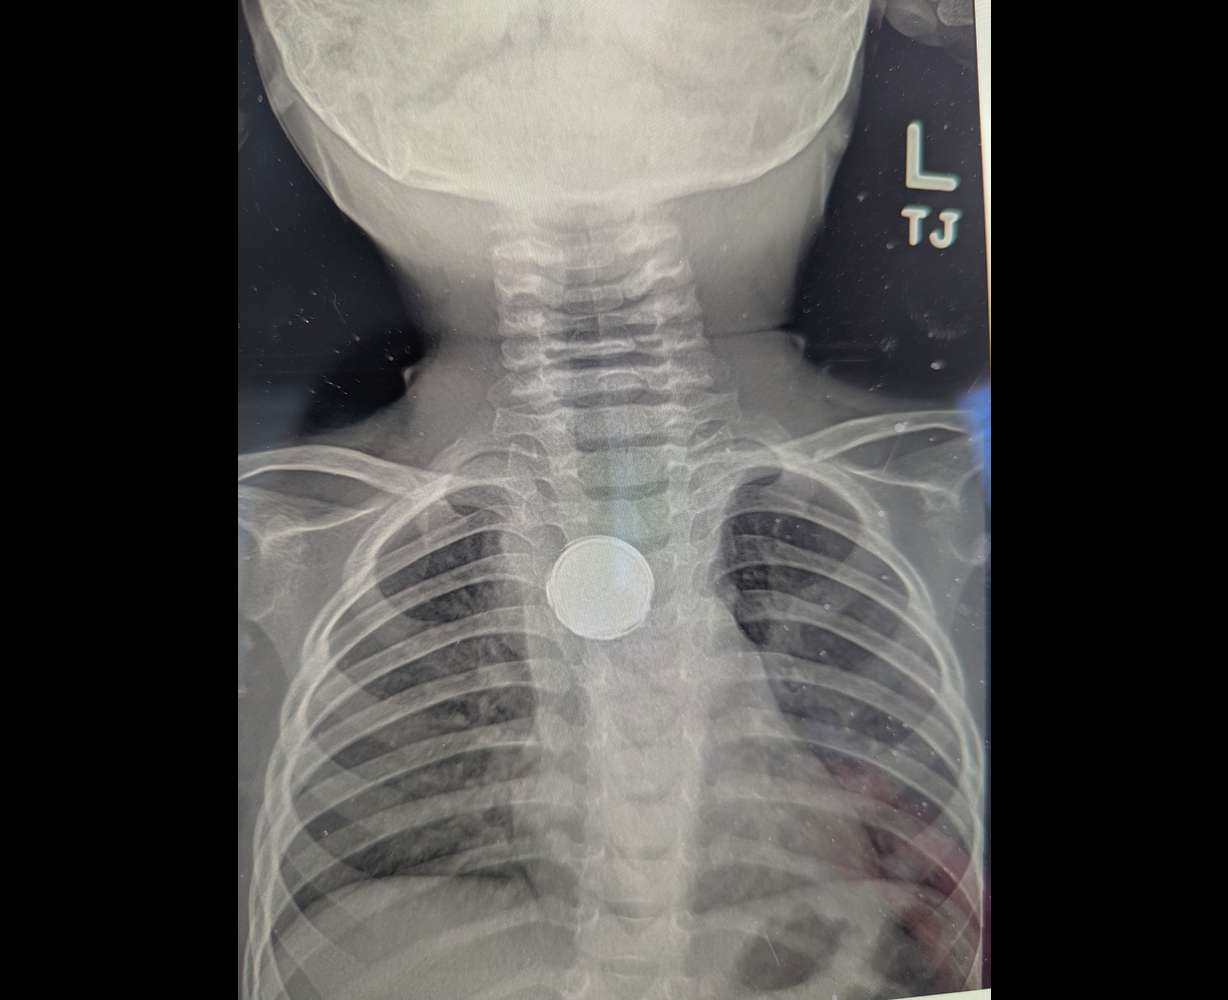

Two months of trips to doctors did not help, with Luke being diagnosed with everything from acid reflux to an ear infection. When an X-ray was finally ordered, doctors could see the problem: Luke had swallowed a battery that became stuck in his esophagus. This could have fatal consequences if it was left there.

"They found out it was a button battery ... and they were surprised that he was alive," said KC McMillan, Luke's father.